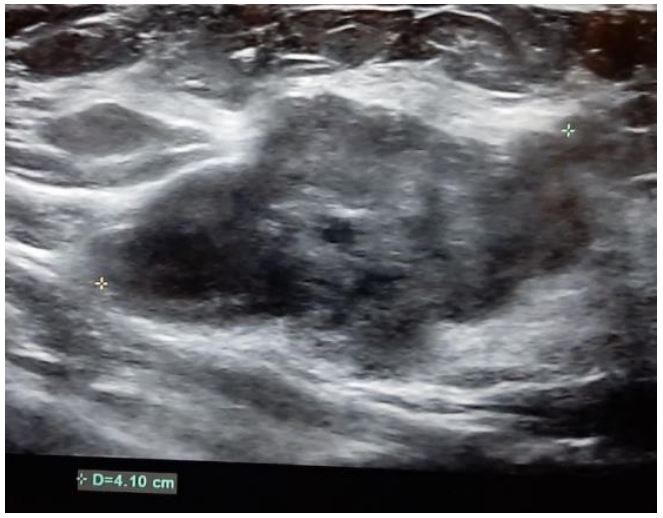

Initially, 4 cm right-sided breast mass was identified on ultrasound (Figure 1). From there, a core needle biopsy was performed, which demonstrated a fibroadenoma. However, the histology from the ensuing lumpectomy demonstrated the presence of a malignant PT. After several courses of radiotherapy, the discovery of the right-sided axillary lymph node necessitated PET-CT, which showed high intake of FDG (Figure 2). The corresponding core needle biopsy confirmed that it contained metastasized PT. After performing bilateral mastectomy with right axillary lymph node dissection, the histology proved that the breasts were clear, but that 1/16 lymph nodes contained PT. Significantly, the occurrence of an additional axillary mass a couple months later prompted an abdominal and chest CT. This demonstrated metastases in the axillary, mediastinal, and retroperitoneal lymph nodes, with liver metastasis (Figures 3 and 4). No further biopsies were performed, and follow-up abdominal and chest CT demonstrated that the metastases had increased in size (Figures 5 and 6).

Figure 1: Ultrasound demonstrating a 4 cm right breast mass with irregular borders.